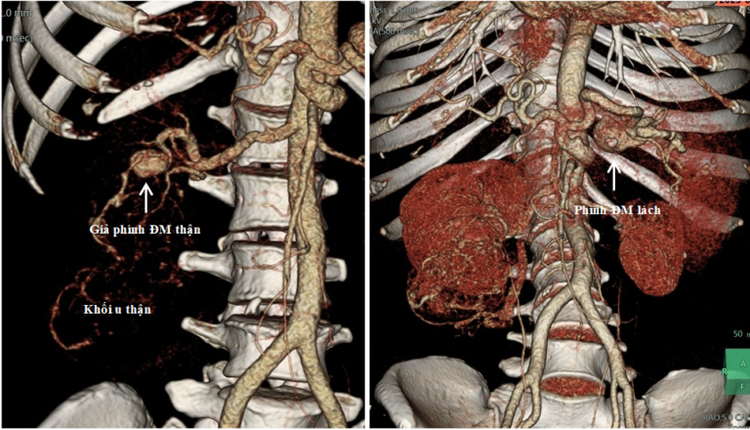

Thật bất ngờ, sau khi chụp phim, sử dụng các kỹ thuật tái tạo ảnh và dựng hình hiện đại, các bác sĩ còn phát hiện nhiều bệnh lý phối hợp bên trong ổ bụng của người bệnh, bao gồm: (1) xơ gan điển hình, (2) khối u thận phải kích thước lớn (u mạch cơ mỡ, kích thước 8,5 x 6,5 cm) và có túi giả phình nhánh động mạch thận nuôi khối u (1,9cm), và (3) khối phình động mạch lách kích thước lớn (3,0 cm).

Hình ảnh khối u thận và giả phình nhánh động mạch thận nuôi u (phải) và hình phình động mạch lách (trái) trên phim chụp cắt lớp vi tính 128 dãy có sử dụng kỹ thuật dựng hình 3D mạch máuHình ảnh khối u thận và giả phình nhánh động mạch thận nuôi u (phải) và hình phình động mạch lách (trái) trên phim chụp cắt lớp vi tính 128 dãy có sử dụng kỹ thuật dựng hình 3D mạch máu